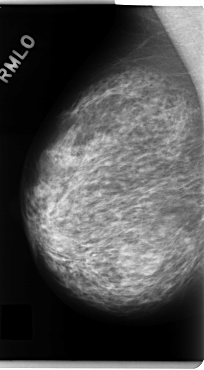

C_0130_1.RIGHT_MLO

RIGHT_CC LINES 4720 PIXELS_PER_LINE 2504 BITS_PER_PIXEL 12 RESOLUTION 50 NON_OVERLAY

RIGHT_MLO LINES 4808 PIXELS_PER_LINE 2648 BITS_PER_PIXEL 12 RESOLUTION 50 NON_OVERLAY